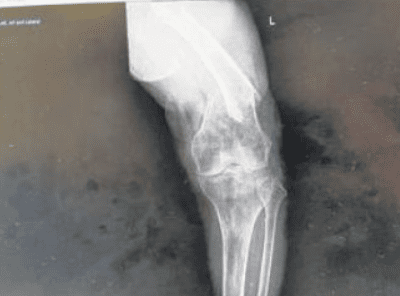

原本就对女佣说辞半信半疑的他不再相信,带母亲去医院检查后,发现母亲的脚已经严重骨折了!

受访者母亲的伤情已经相当严重了,图源:新明日报

最终,这才是导致他母亲摔倒并且大腿骨折的罪魁祸首......直到现在,他的母亲依旧没有完全康复,还在住院中。